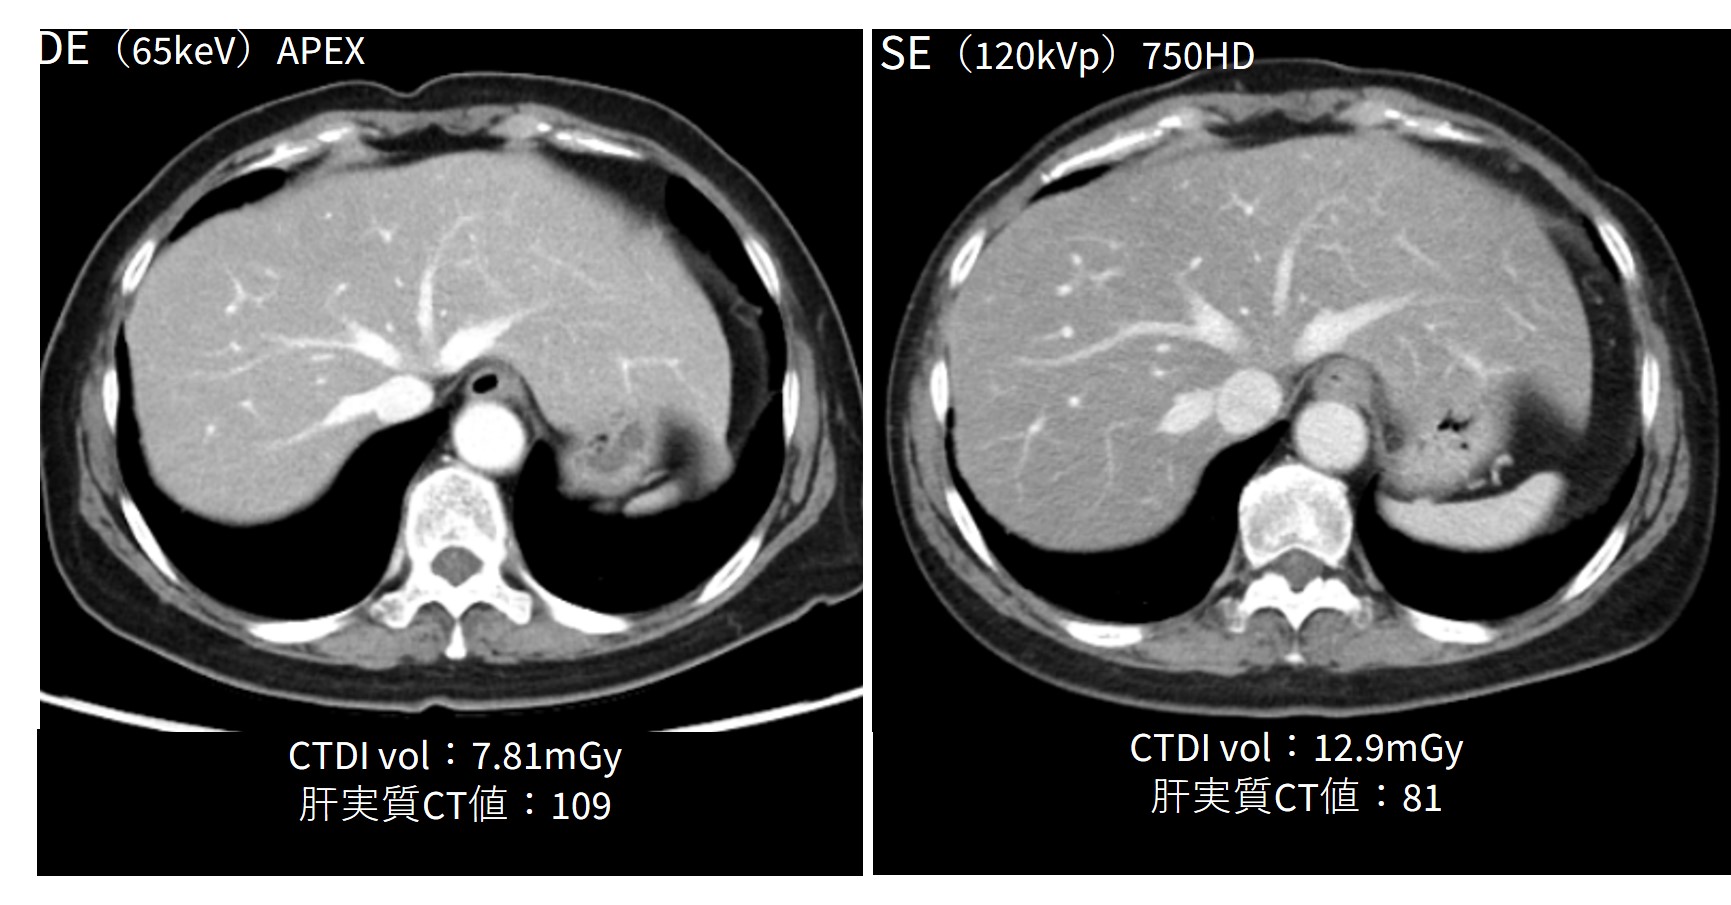

DLIRの恩恵もあり、SEとほぼ同等の画像で、さらに被ばくも低減ができている(Fig.2)。

造影に関しては、ルーチンで65keVを使用している。低keVを用いて造影剤量を下げる使用方法も十分にできるが、放射線科医からの要望で診断能を上げる使用方法を選択している。DEの画像に関して、他科医師からの画像の違和感などの指摘を受けたことはない。

revolutionapexelite_aomori06.jpg

Fig.2 DE with TFDLで画質は担保したまま線量を下げ、CT値も上昇